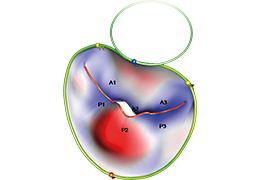

Performs 3D reconstruction and volume rendering.

Multi-planar slicing.

Oblique slicing.